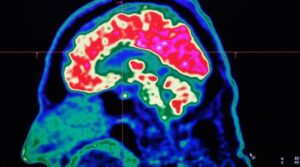

ایک پوسیٹرون اخراج ٹوموگرافی اسکینر کے ذریعہ لیا گیا انسانی دماغ کی ایک تصویر ، جسے پی ای ٹی اسکین بھی کہا جاتا ہے ،